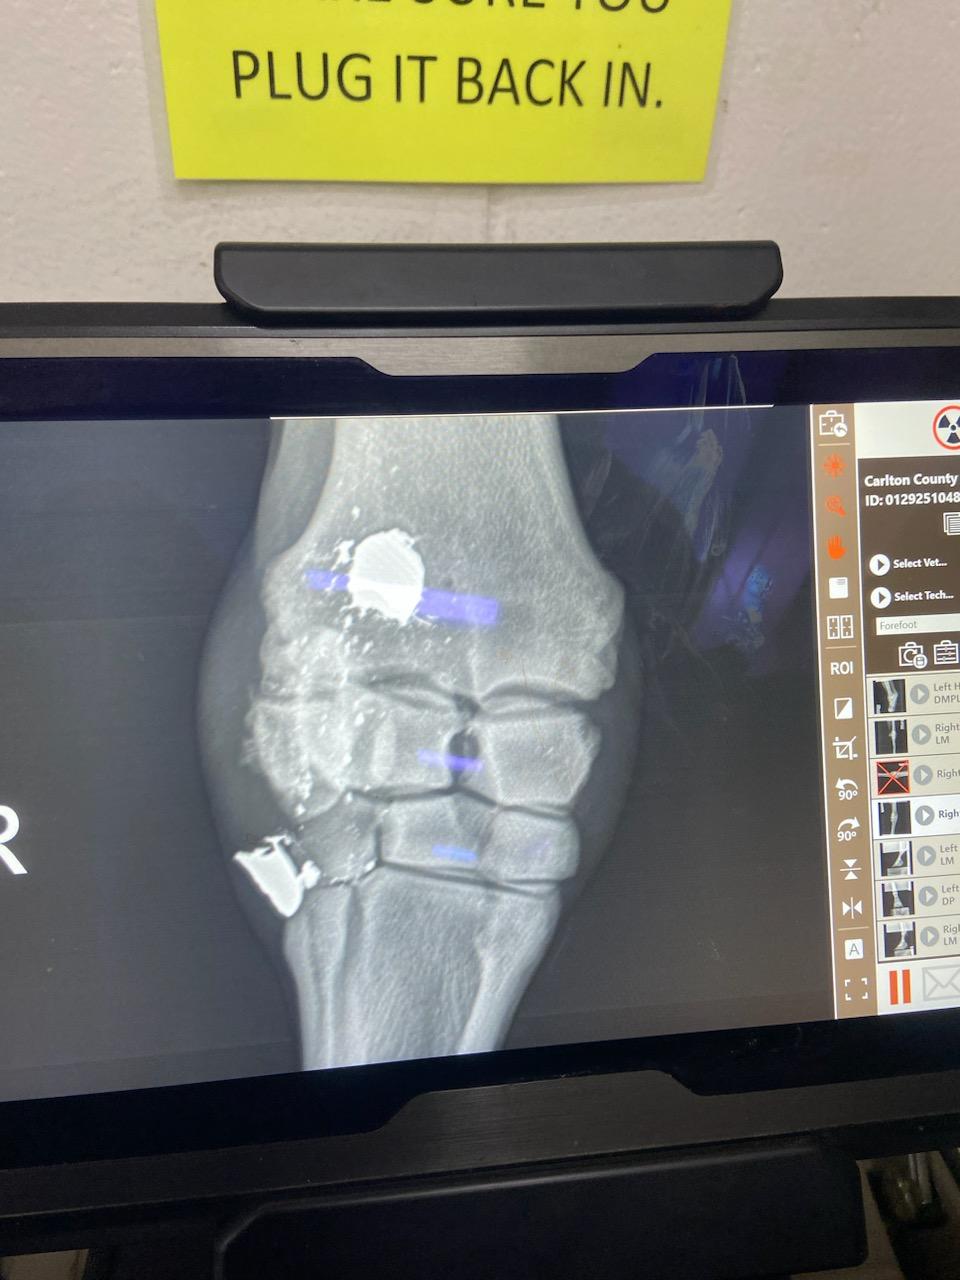

Lieutenant Dan is a 2020 miniature stallion who came to us from a January 2025 Carlton County case. He is MISSING the lower part of his left hind leg and has been living this way for at least a couple of years. We started his care by doing complete discovery vetting to determine the best way to proceed (a prosthetic specialist is included in the process) in order to provide him with the most humane care possible and to do what is in his best interest. He was sedated, radiographed, and his leg stump was bandaged for protection after a cast was made of it to make a prosthetic. He also had blood pulled for a general workup and Coggin’s testing. The big news to come out of the exam is the fact that he has bullet fragments in one of his front legs (seen on radiographs) which makes us suspect that this may be related to his missing hind leg as well. This little guy is truly a survivor! Thank you so much to everyone at Anoka Equine Veterinary Services for taking such an interest in Lt. Dan’s case and helping to make sure he receives what he needs with their excellent care. His comfort is our main concern and so far he seems to be doing quite well with his prosthetic.